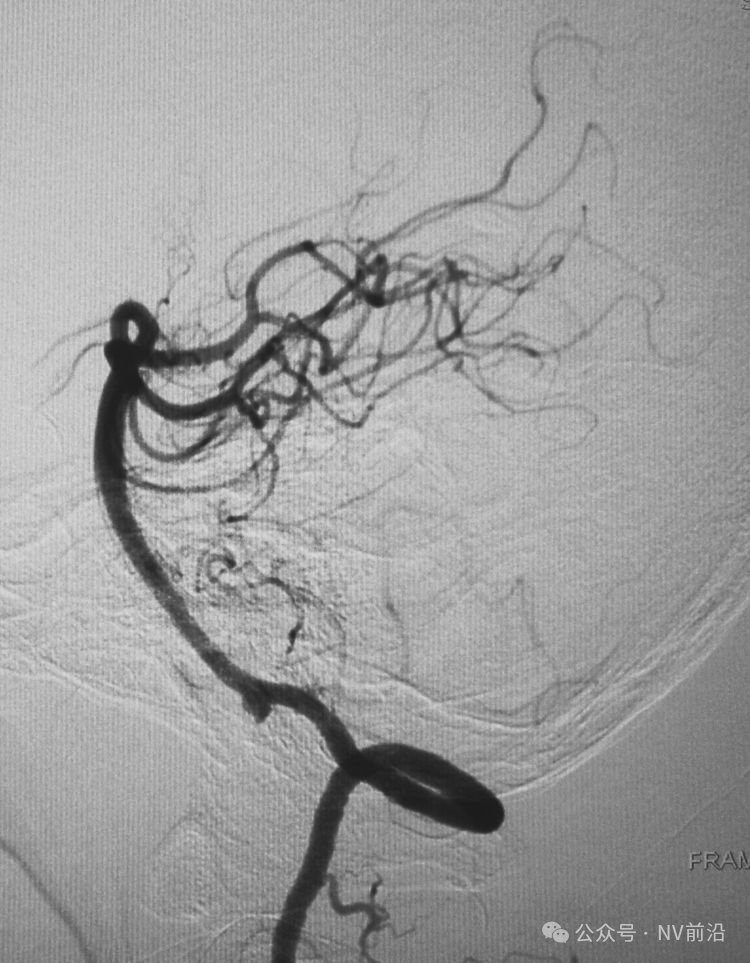

工作位造影

Traxcess 14微导丝可以进入瘤腔,但头端塑成S形的Echelon 10微导管无法跟入。

将微导管在虹吸弯处成襻,越过瘤颈,管头折返钩入瘤腔,即所谓回马枪技术。